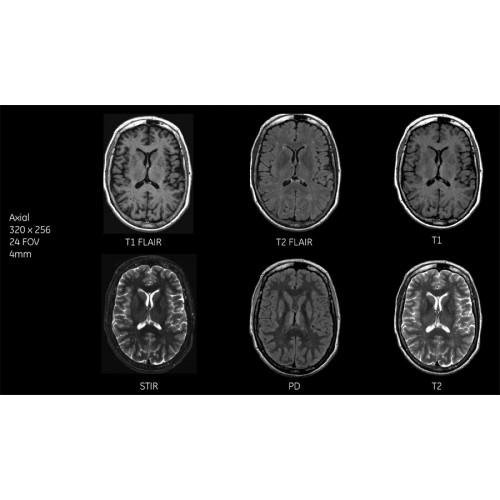

Детализация изображений

Система SIGNA Pioneer воплощает поразительные достижения в области визуализации. Передовая технология Total Digital Imaging (TDI) позволяет добиться большей четкости изображений и на четверть повысить соотношение сигнал/шум.

TDI построена на трех базовых компонентах:

• Технология Direct Digital Interface (DDI) использует независимый аналого-цифровой преобразователь для оцифровки сигнала от каждого из 97 радиочастотных каналов, что обеспечивает значительное увеличение качества за счет уменьшения фонового шума.

• Технология Digital Micro Switching (DMS) — это следующее поколение технологий радиочастотных катушек, основанное на замене аналоговых схем блокировки сверхбыстрыми микропереключателями (MEMS), что делает возможным быстрое переключение катушек для дальнейшего расширения возможностей визуализации с нулевым TE.

• Технология Digital Surround Technology (DST) — это новая технология объемной оцифровки данных, объединяющая сигналы от каждого элемента катушки. Прекрасное соотношение сигнал/шум и чувствительность поверхностных катушек в сочетании с превосходной однородностью и высокой проникающей способностью встроенной радиочастотной катушки — все это позволяет создавать качественные изображения не только позвоночника, но и всего тела.

Благодаря революционному программному пакету Silent Suite уровень шума снижается до 77 дБ, что всего на 3 дБ выше уровня окружающей среды. Программный пакет Silent Suite теперь включает полный пакет приложений для исследования ЦНС (T1, T2 FLAIR, DWI10, МРА). Кроме того, мы расширили возможности визуализации Silent за пределы ЦНС для исследований скелетно-мышечной системы и позвоночника. Silent Suite – платформа, содержащая в себе все импульсные последовательности для бесшумного сканирования.